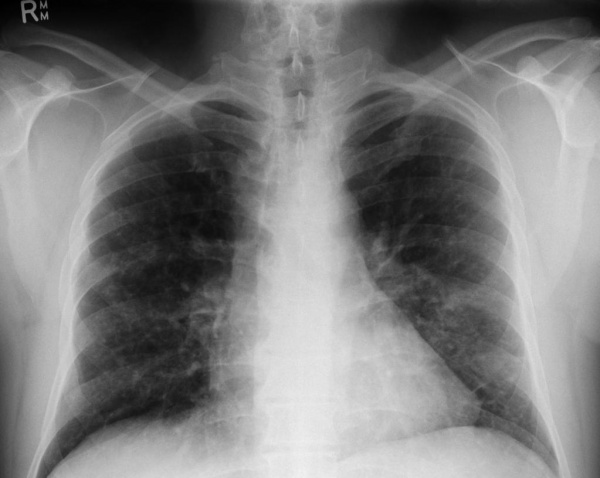

- Инструментальные исследования. При рентгенографии скелета находят очаги деструкции и остеолизиса, особенно выраженные в плоских костях черепа и длинных трубчатых костях. На рентгенограмме органов грудной клетки видны двусторонние мелкоочаговые затемнения (узелки, буллы), усиление легочного рисунка. Для более точной визуализации легочной ткани назначается компьютерная томография легких высокого разрешения, позволяющая определить их ячеистую деформацию. Результаты измерения функции внешнего дыхания (спирографии) показывают ухудшение диффузионной емкости легких.

![Рентгенография легких. Диффузные двусторонние узловые затемнения и небольшие кисты в верхней и средней доле]()

Рентгенография легких. Диффузные двусторонние узловые затемнения и небольшие кисты в верхней и средней доле